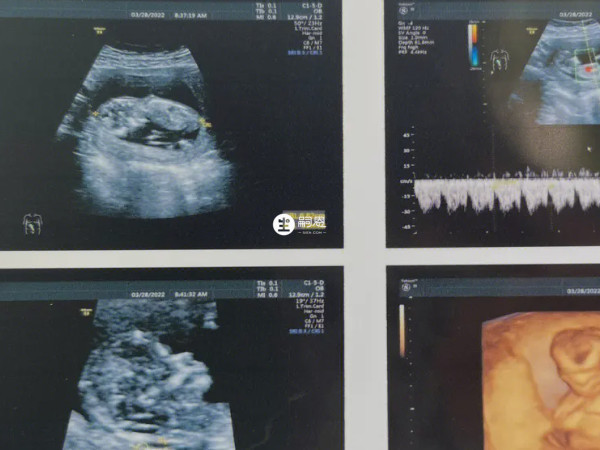

对于孕妇来讲,大多都会在孕12周左右做NT检查,很多人表示NT单子能够看出胎儿的性别。其实在NT检查单上面,怀女儿的特征和怀儿子的特征是不一样的,相信有许多的朋友是想要生女儿的。已生女儿的NT单子什么样,来看看已生女儿的网妈们,公布出来的女宝NT单子上比较明显的几个特征:

孕12周时,胎儿的外生殖器已经初步发育,而由于男女之间存在差异,因此在B超下表现也不同,如果孕妇怀的女孩,那么在图像上会看到有明显的三条线,这是女孩的性别特征,若是怀的男孩,会看到有三个亮点,或者是一个小突起,这是男孩的性别特征。

可以通过尾椎与身体所成角度进行判断,胎儿在11周左右,无论男女,在双腿之间会有一个生殖结节的组织,到孕12周时男女之间在B超下就会形成差异,如果NT图像上尾椎与躯干平行,中间几乎为零度角,那就是生女儿,若身体呈45度角,后脊背柱形成圆弧状,那就是生儿子。